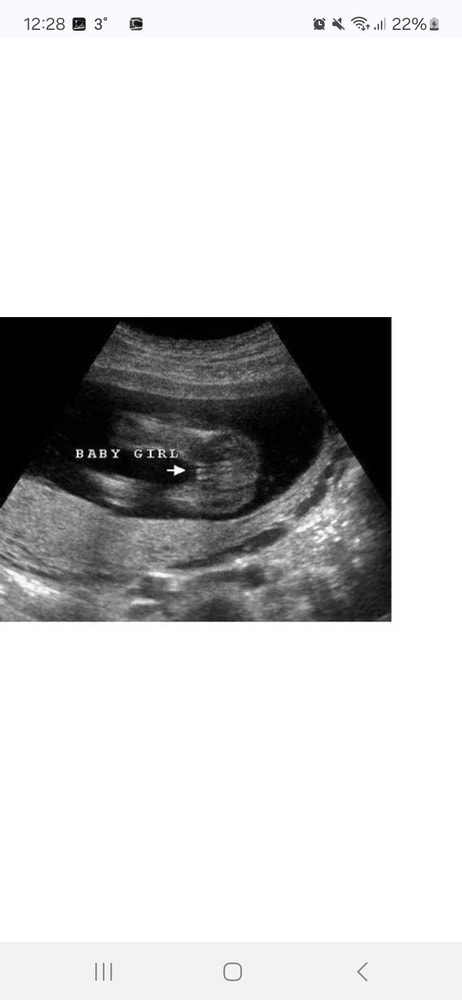

Маша, примеры Изображение Примеры из интернета,мне кажется ваш случай девочка Изображение

10.11.2025

Маша, у меня на каждом узи уже смотрели ) вот так было в 20 недель мальчиком и не пахло Изображение

09.11.2025

Татьяна, ну да у вас четко видно ))